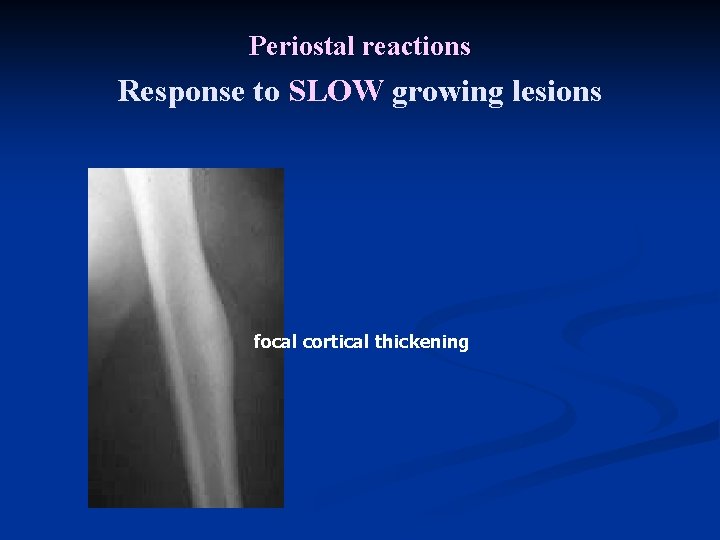

Periostal reactions Response to SLOW growing lesions focal cortical thickening